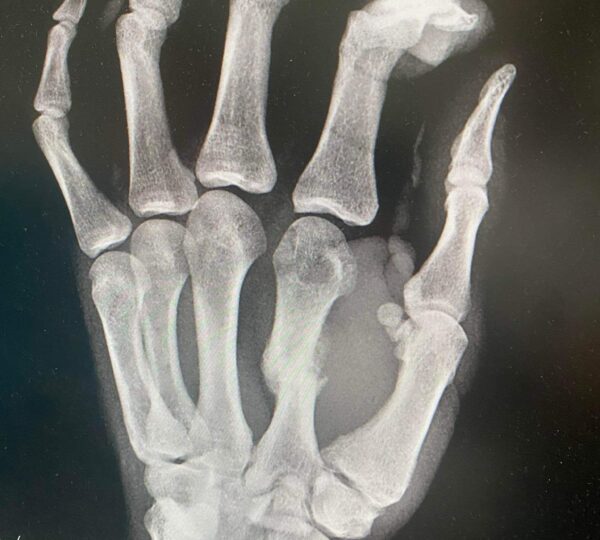

Zlomeniny rúk, prstov a nôh patria medzi najčastejšie športové úrazy.. Ich liečba býva zdĺhavá a náročná – najmä pre športovcov, ktorí potrebujú rýchlo a bezpečne obnoviť plnú funkčnosť. Prípad zlomeniny zaprstnej kosti zo dňa 4. 6. 2024, následná osteotómia 27. 10. 2024 a intenzívna liečba ukončená 22. 12. 2024 ukazuje, že aj komplikované zranenie sa dá zvládnuť rýchlo a bezpečne.

• Zranenie: 4. 6. 2024 – zlomená zaprstná kosť

• Operácia (osteotómia): 27. 10. 2024

• Začiatok liečby: 28. 10. 2024

• Koniec rehabilitácie: 22. 12. 2024

• Kompletný návrat do zápasu: 6. 2. 2025

Osteotómia je chirurgický zákrok, pri ktorom sa kosť prerezáva a presne nastaví tak, aby mohla správne zrast. Po takejto operácii predstavuje hlavnú výzvu najmä kvalita zhojeného kostného tkaniva, opuch, bolesť a obmedzenie pohyblivosti. Práve terapia LIMFA tu zohrala kľúčovú úlohu.